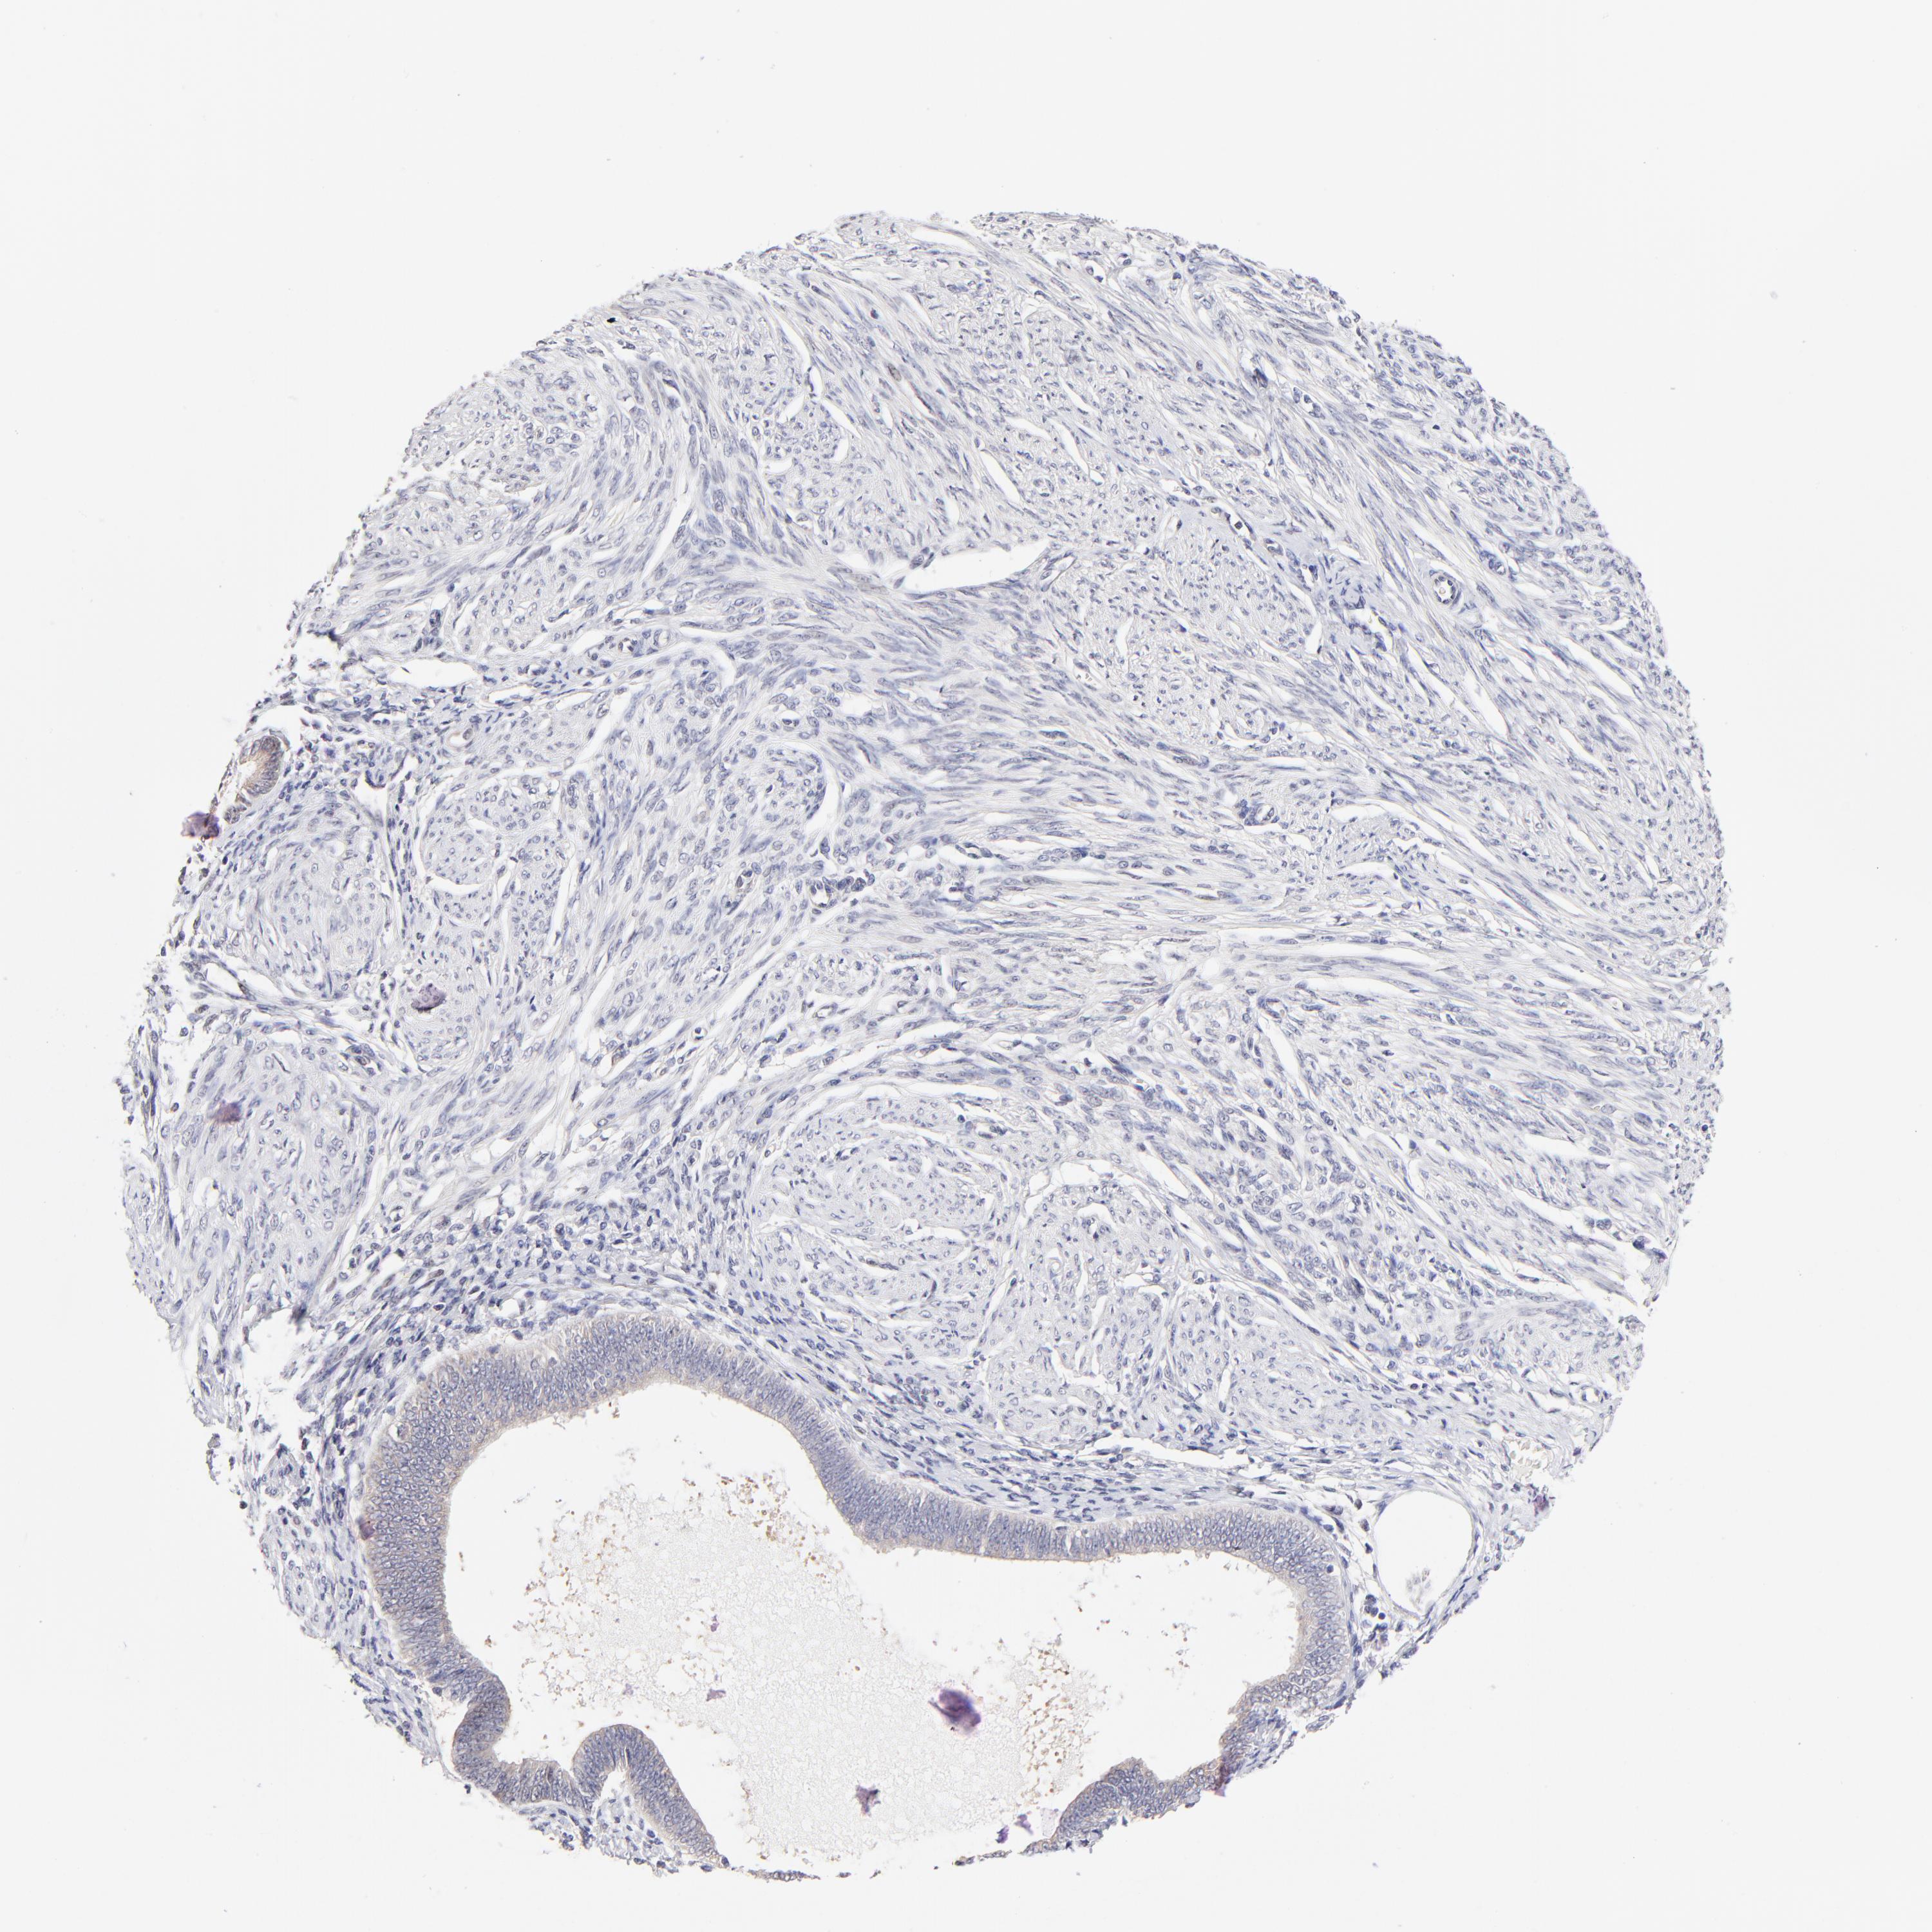

ENDOMETRIAL CANCER - Protein expressioni

A mouse-over function shows sample information and annotation data. Click on an image to view it in a full screen mode. Samples can be filtered based on level of antibody staining by selecting one or several of the following categories: high, medium, low and not detected. The assay and annotation is described here.

Note that samples used for immunohistochemistry by the Human Protein Atlas do not correspond to samples in the TCGA dataset.

Antibody stainingi

Antibody staining in the annotated cell types in the current human tissue is reported as not detected, low, medium, or high, based on conventional immunohistochemistry profiling in selected tissues. This score is based on the combination of the staining intensity and fraction of stained cells.

Each image is clickable and will lead to virtual microscopy that enables deeper exploration of all samples and also displays staining intensity scores, fraction scores and subcellular localization as well as patient and tissue information for each sample.

Antibody HPA003204

Staining

High

Medium

Low

Not detected

Intensity

Strong

Moderate

Weak

Negative

Quantity

>75%

75%-25%

<25%

None

Location

Nuclear

Cytoplasmic/membranous

Cytoplasmic/membranous,nuclear

Adenocarcinoma, NOS